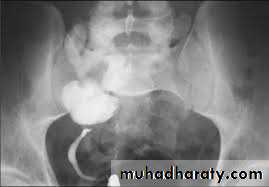

Grades

Grade I Contrast into non-dilated ureter

Grade II Contrast into renal pelvis and calyces; no dilatation

Grade III Mild dilatation of ureter; pelvis, and calyces

Grade IV Dilated ureter becomes slightly tortuous; moderate dilatation of pelvis and blunting of calyces

Grade V Severe ureteric dilatation and tortuosity; gross dilatation of pelvis and calyces